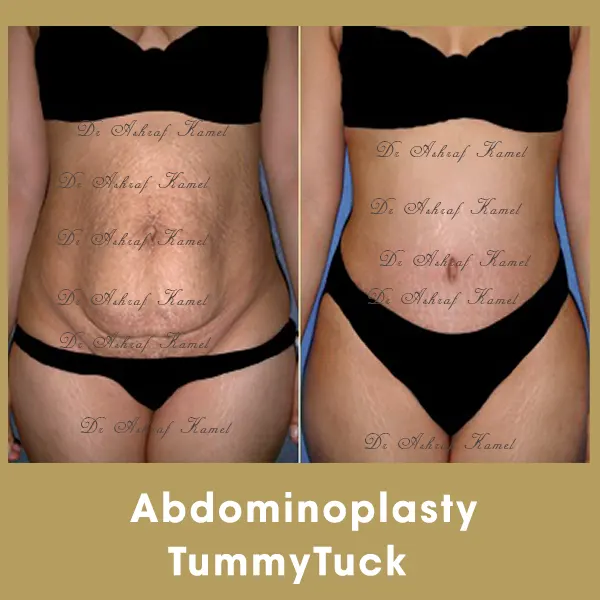

صور حالات مرضى

اشتهر بتقديم احدث تقنيات طب التجميل والجراحات التجميلية وعمليات تنسيق القوام، تكبير وتصغير وشد الثدي وتجميل الأنف وعلاج الترهلات، شد الذراعين و ازالة الترهلات، رفع الأرداف و علاج جراحات السمنة ونحت العضلات والـ6 باكس عالي التحديد، شفط الدهون بالفيزر والجي بلازما واحدث التقنيات بالخريطة الالكترونية، تجميل الجفون، تجميل الاذن وعلاج الاذن الوطواطية.